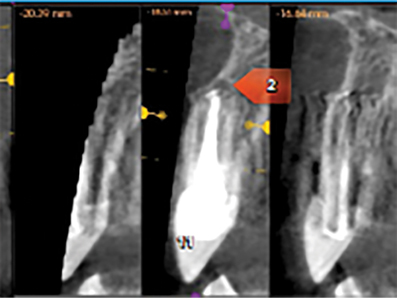

A CBCT done in September 2018 and revealed a knife edge ridge in the 23-site requiring GBR (guided bone regeneration) and periapical rarefying osteitis around 11,22,24, teeth which were previously endodontically treated. (Figs. 7,8,9). After an endodontic consult, a diagnosis of acute apical periodontitis was made, and treatment options for these teeth presented to the patient that included- re treatment, extraction or apicoectomy. Three months post implant removal under coverage of premedication (Amoxicillin 500mg tid for 2 days) apicoectomy of 22 and 24, in combination with periodontal surgery (GBR) was performed. Local anesthesia (LA) was achieved with 1.5 carps Lido 2%, 1:100K Epi and 2 carps Ultracaine 4% 1:200K Epi. A full thickness flap elevation (FTF) was done on the buccal and palatal aspects with remote vertical releases on the buccal for access to GBR on site 23. Apicoectomy was performed in 22/24 with ultrasonic root end preparation and filled with MTA (mineral trioxide aggregate). A significant vertical defect was seen in the 23 site with loss of buccal and palatal bone walls but the proximal walls were intact. For the cortical perforations; a composite mixture of 50:50 allograft: xenograft particulate bone was used to graft the deficient ridge. The bone graft was covered with a titanium reinforced barrier membrane (Cytoplast™ Ti-250) which was in turn covered by an amnion-chorion barrier membrane (BioXclude®). The membranes were secured with stabilizing sutures and a periosteal releasing incision was made for the buccal flap for tension-free primary closure with 4-0 PTFE sutures and 5-0 chromic gut sutures. Hemostasis was achieved and post operative instructions were reviewed with the patient. The patient was asked to continue taking the Amoxicillin (Amox) for a period of 7 days, additional Rx given for T3 (x25 tabs) 1-2 q4-6h prn pain and Decadron 4 mg once daily for 4 days (loading dose = 8 mg). The patient was seen for a 3-week postoperative visit and the surgical sites appeared to be healing well characterized by minimal inflammation and patency of the wound closure. During a 3month post operative follow up, a 2×2 mm membrane exposure was detected coronally, but the soft tissues were healthy and left to continue the natural course of healing.

Fig. 7

Fig. 8

Fig. 9